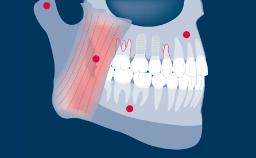

无论治疗的位置或程度如何,种植治疗计划应始终以修复为导向。这可确保种植体植入满足义齿的需求,并与期望的最终效果相一致。为了实现最佳的效果,修复计划应包括:考量所有相关修复因素,并进行适当的诊断检查,在此基础上制定种植义齿和支持种植体的具体计划。

- 概述种植义齿及其支持种植体的具体治疗计划要点